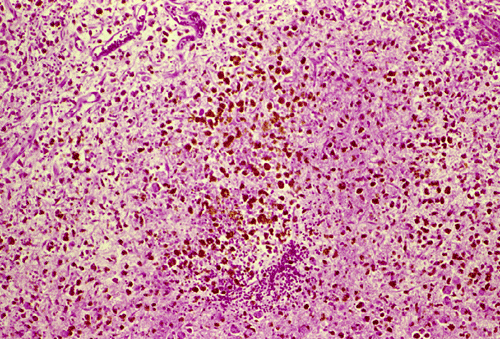

Histopathology: The hemorrhage, not surprisingly, is composed of blood (Panel B). At the periphery of the hemorrhage are areas that are heavily infiltrated by macrophages accompanied by substantial hemosiderin depositions (Panel C). On medium magnification, the blood vessel walls seems to be thickened and some ill-defined deposition are present in the wall (Arrow in Panel D). Immunohistochemistry for amyloid-b (Ab) was performed and the depositions in the vessel wall are positive.